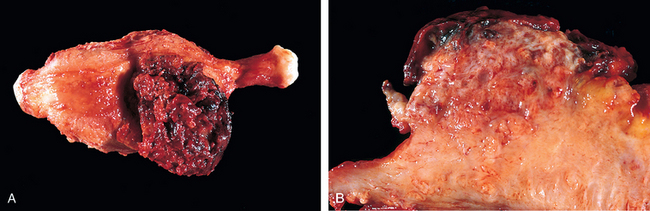

Teratomas

Mature (Benign) Teratomas.

Morphology. Benign teratomas are bilateral in 10% to 15% of cases. Characteristically they are unilocular cysts containing hair and cheesy sebaceous material (Fig. 22-43). On section, they reveal a thin wall lined by an opaque, gray-white, wrinkled epidermis. From this epidermis, hair shafts frequently protrude. Within the wall, it is common to find tooth structures and areas of calcification.

image

FIGURE 22-43 Opened mature cystic teratoma (dermoid cyst) of the ovary. Hair (bottom) and a mixture of tissues are evident.

On histologic examination the cyst wall is composed of stratified squamous epithelium with underlying sebaceous glands, hair shafts, and other skin adnexal structures (Fig. 22-44). In most cases structures from other germ layers can be identified, such as cartilage, bone, thyroid tissue, and neural tissues. Dermoid cysts are sometimes incorporated within the wall of a mucinous cystadenoma. About 1% of the dermoids undergo malignant transformation (e.g., thyroid carcinoma, melanoma, but most commonly, squamous cell carcinoma).

FIGURE 22-44 Benign cystic teratoma. Low-power view of skin (right edge), beneath which there is brain tissue (left edge).